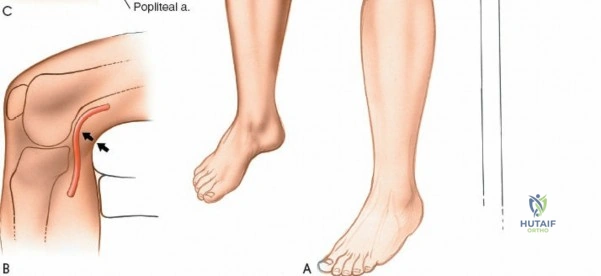

- Vascular Injury:

- Incidence: Extremely rare (<0.01%). Damage to the popliteal artery or its branches.

- Management: Urgent vascular surgical consultation and repair.